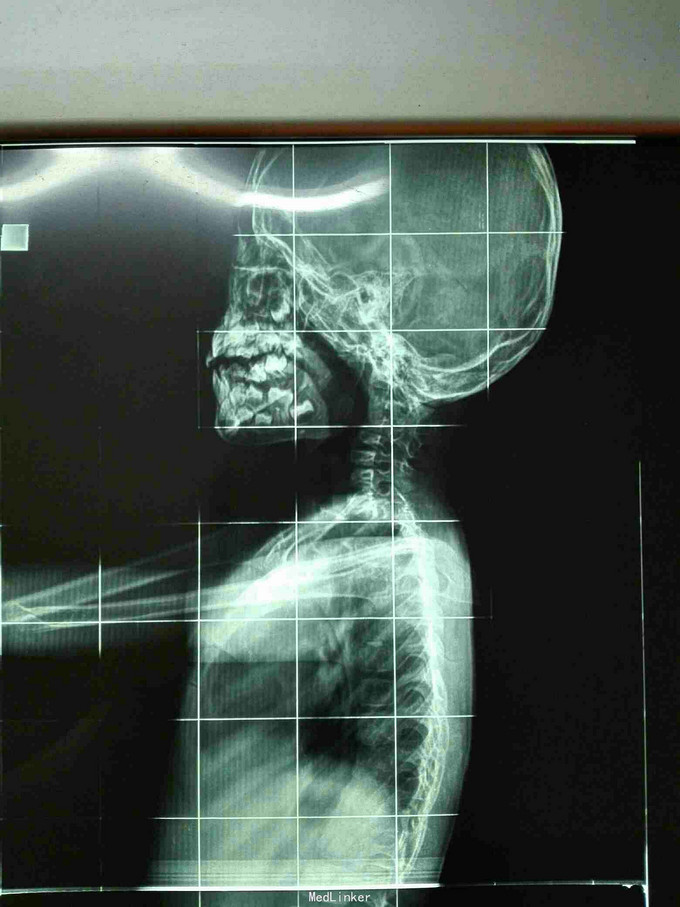

先天脊柱畸形

先天脊柱畸形8年。

严重脊柱畸形病例

先天性脊柱侧凸畸形

脊柱先天畸形